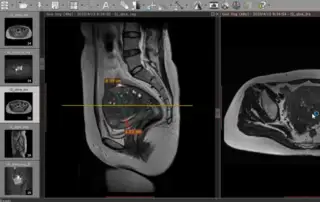

1) Myoma and kissing Ovaries – 2) ICG right pelvic wall lymph node street